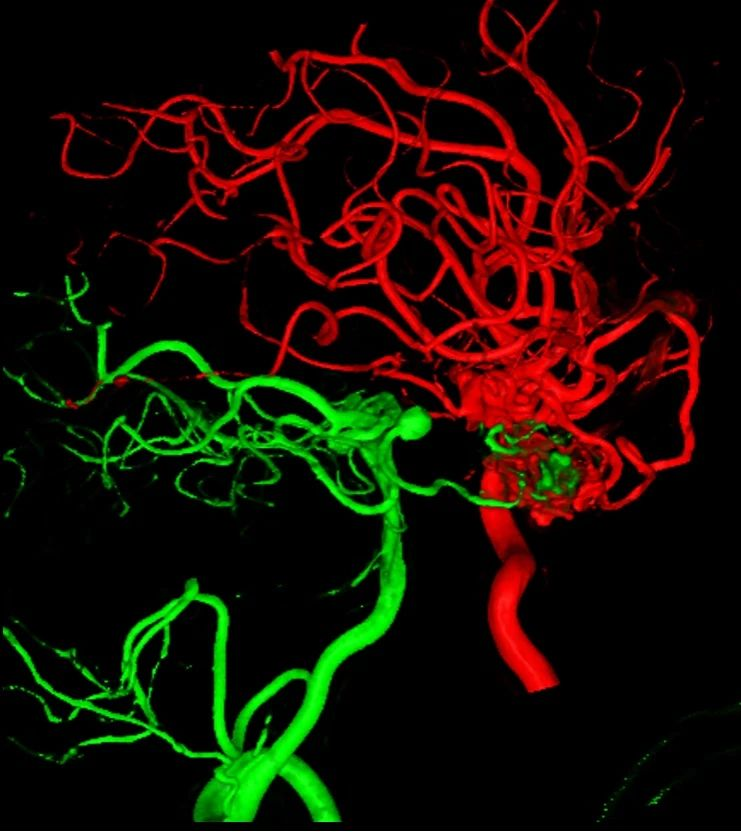

入院后脑血管造影检查提示:右侧颞叶动静脉畸形,由右侧大脑中动脉两分支血管参与供血,右侧大脑后动脉一分支血管参与供血,畸形团大小约1.1*1.3cm,通过侧裂静脉经皮层静脉引流入上矢状窦前部;并可见右侧大脑后动脉供血畸形团的分支血管血流相关性动脉瘤两枚。